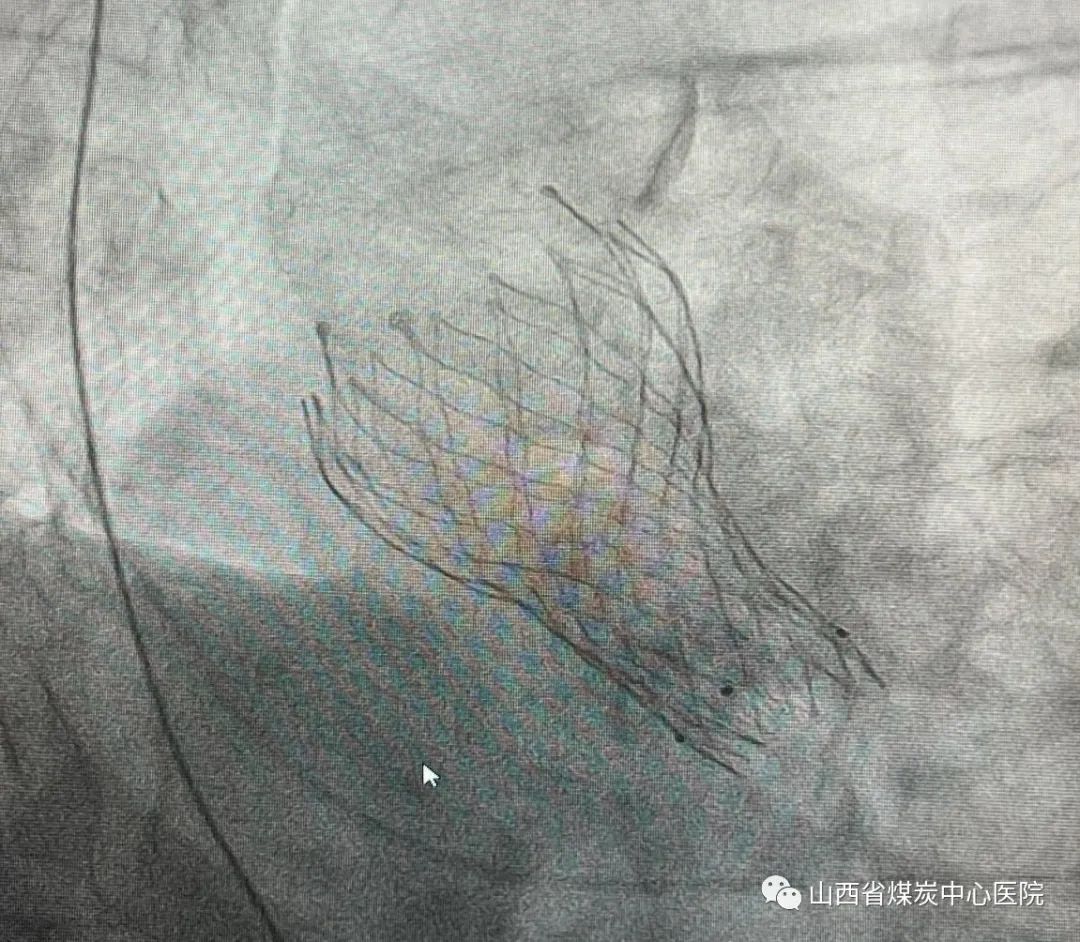

成功植入患者体内的主动脉瓣瓣膜